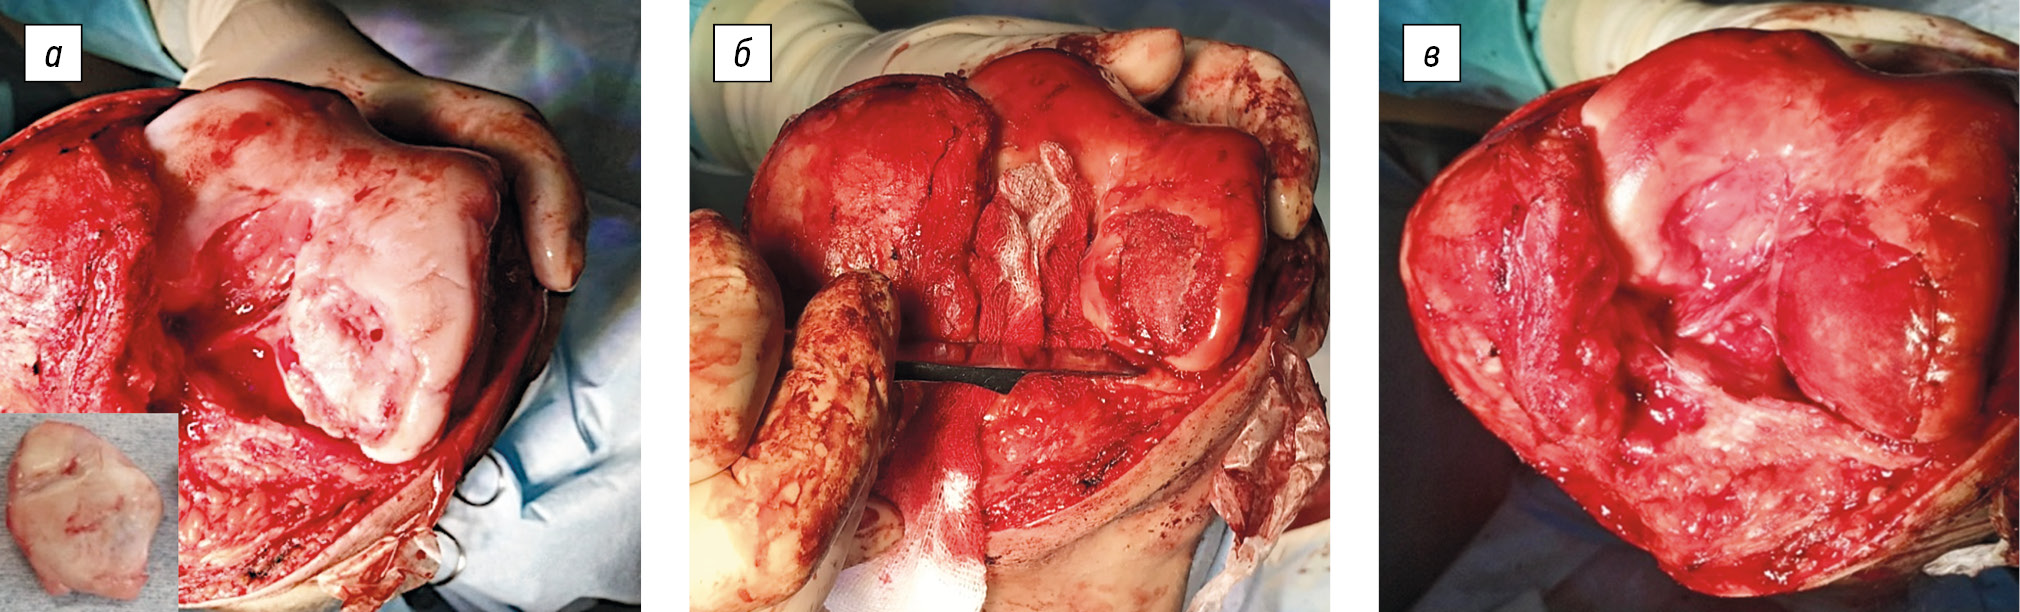

Considering the patient’s condition as well as the size and depth of the defect and associated pathological changes, osteochondral reconstruction of the lateral condyle of the left femur was indicated. Accordingly, a lateral parapatellar approach to the left knee joint was performed. The patella was mobilized and retracted medially. The pathological site was visualized with the knee flexed. The free osteochondral body was removed. Scar tissues and the underlying sclerotic bone were excised until the “bloody dew” sign could be observed. An autologous graft from the iliac crest was impacted into the postresection defect. A collagen membrane, tailored to match the size of the cartilage defect, was placed over the graft site and secured with interrupted sutures (Polysorb 6/0). The surgical steps are depicted in Figure 6.

Fig. 6. Intraoperative images of patient M.: a, osteochondral defect of the lateral femoral condyle, with the removed osteochondral body; b, post-resection defect filled with an autologous bone graft; c, the area of bone grafting was covered with a collagen membrane secured with interrupted sutures.